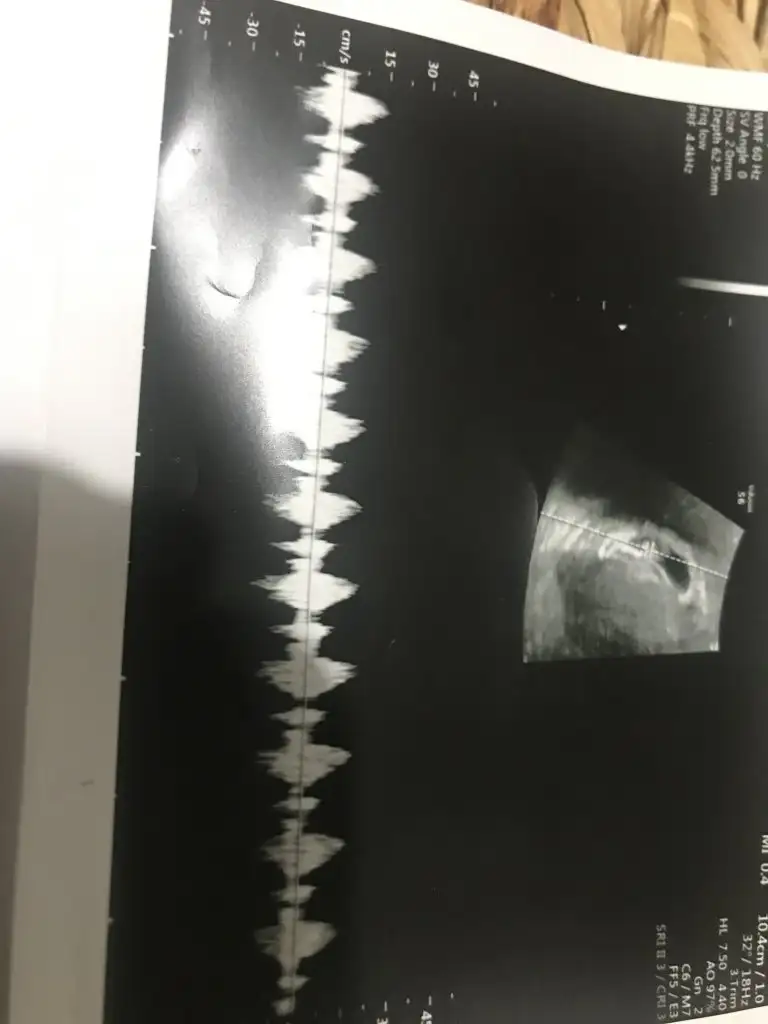

banada bakar misin canim doktorlar bir tahminde bulundular ama tam olarak demediler

7+4 teki ilk ultrason fotoğrafı tahmininiz nedir karından ultrason

Eklentiler